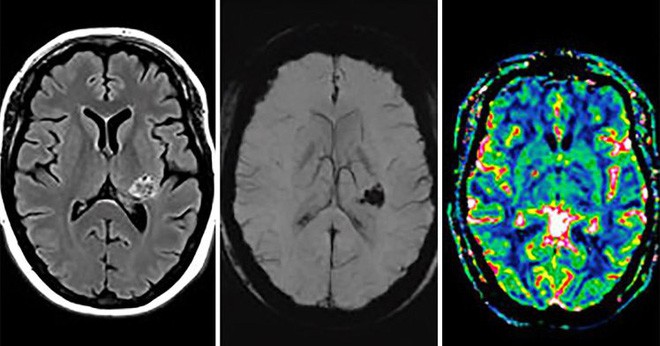

Một người phụ nữ cho biết cô nghe được những lời nói siêu nhiên. Bác sĩ đã chụp cắt lớp não của người phụ nữ này. Không ai còn dám nói cô bị cho là tâm thần sau khi xem kết quả.

Sau khi tiến hành chụp cắt lớp cho bệnh nhân, quả thật suy đoán của họ không hề sai. Bên trong não của người phụ nữ này phát hiện có một khối u đang phát triển. Giáo sư tâm thần và thần kinh học Sebastian Walther cho biết: “Khối u nằm trên khu vực mạng lưới thần kinh quan trọng ảnh hưởng đến nhận thức về giọng nói. Vì vậy bệnh nhân đã nghe được những ảo thanh, và khiến cho cô tin rằng mình đang nói chuyện với Chúa”.

Cộng thêm với niềm tin tôn giáo mạnh mẽ, người phụ nữ này dần dà đã phải đối mặt với sự ảo tưởng nghiêm trọng. Khối u được xác định phát triển ở vùng dưới đồi, phần lớn nhất của vùng não trung gian, gây ra các biểu hiện tương tự như bệnh nhân mắc phải chứng tâm thần phân liệt.

Các nhà nghiên cứu, những người đã dành nhiều năm tìm hiểu về bệnh tâm thần phân liệt, tin rằng trường hợp của bệnh nhân này sẽ giúp cho họ có thể hiểu rõ hơn về tình trạng này. Họ cho biết, đây là bằng chứng cho thấy các triệu chứng tâm thần phân liệt không được kích hoạt trên toàn bộ não mà là sự gián đoạn cụ thể ở một số khu vực nào đó.